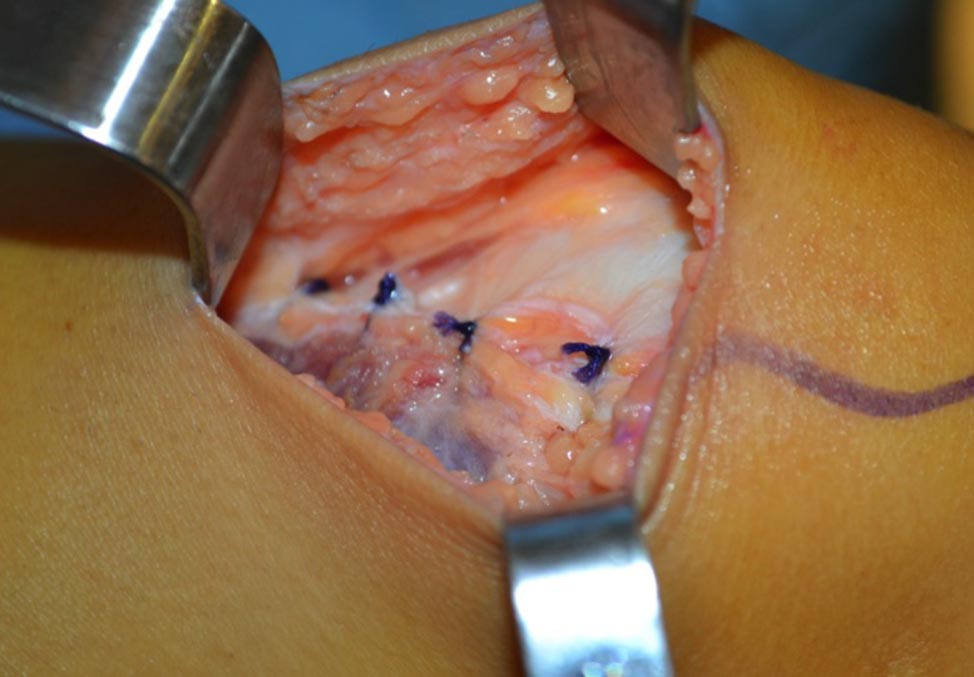

Se toma un injerto del tendón cuadricipital (TC) de espesor completo dejando un margen de 2-3 mm en la zona medial, para permitir un cierre del defecto tendón-tendón. Es importante evitar abrir la cápsula articular. Para ello es conveniente comenzar la disección aproximadamente 3 cm proximal al polo superior de la rótula donde el tendón se encuentra bien diferenciado de la cápsula articular, y luego continuar hacia proximal (Fig. 3). Finalmente se continúa hacia distal con una disección subperióstica hasta la inserción anatómica del LPFM en la rótula. Este gesto permite ganar 1-1.5 cm de longitud final del injerto. Se mantiene la inserción rotuliana del TC y se lo gira sobre sí mismo de modo que la cara posterior quede anterior y viceversa. Se fija el extremo distal del tendón con puntos tipo Krakow y se refuerza la inserción rotuliana con puntos en 8, ambos con suturas no absorbibles tipo Fiberwire. Se diseca el plano entre vasto medial oblicuo (VMO) y el retináculo medial. Se identifica con el arco en C, en un perfil estricto, el punto anatómico de inserción femoral del LPFM. Este paso es crítico al momento de la reconstrucción. En pacientes esqueléticamente maduros utilizamos el punto de referencia radiográfico descripto por Schöttle.7 En pacientes esqueléticamente inmaduros fijamos el injerto en la región epifisaria inmediatamente distal al cartílago de crecimiento (Fig. 4), ya que este punto de referencia no es fiable en pacientes con fisis abierta.8

Se realiza un abordaje medial de 3 cm en el punto identificado previamente. Se coloca un arpón de 5.0 mm con doble sutura (Fig. 5). Se pasa el injerto con una Halsted larga en plano entre retináculo medial y el VMO. Se fija el injerto al arpón con rodilla en 30 grados de flexión. Es muy importante evaluar la tensión que se le da al injerto. Para evitar la hiperpresión o que el injerto quede laxo es indispensable que la rótula pueda trasladarse hacia lateral un 25% de su ancho al colocar la rodilla en extensión. Luego se introduce nuevamente el artroscopio y se comprueba que el tracking rotuliano sea correcto. Posteriormente se cierra el defecto de la toma de injerto avanzando el VMO levemente hacia lateral y distal con puntos continuos de Vicryl 1 (Figs. 6 y 7). Luego se cierra el tejido celular con vicryl 3.0 y la piel con sutura intradérmica de Vicryl rapid 4.0. Se infiltra con bupivacaína las heridas e intra-articular y se colocan apósitos estériles, venda elástica e inmovilizador de rodilla.

Figura 3: Preparación del injerto

Figura 5: Fijación del injerto con un arpón de 5.0mm